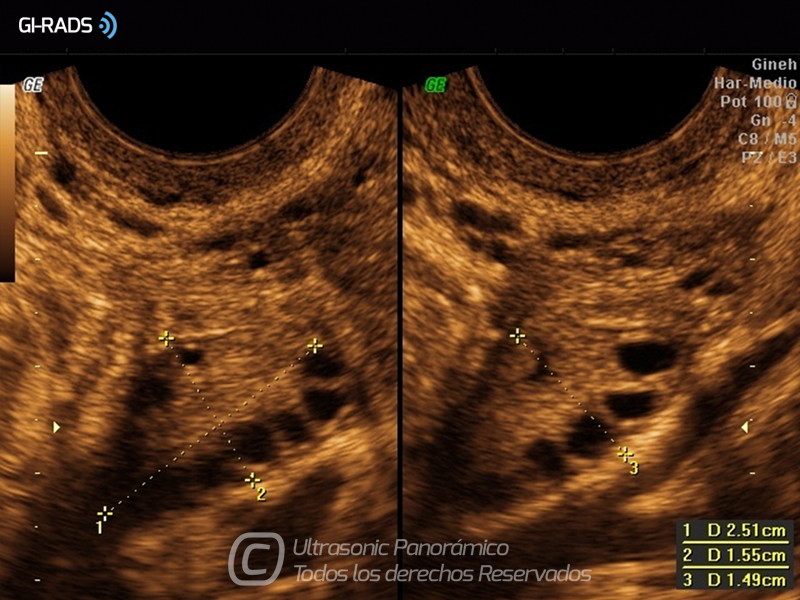

Imágenes Normales

• Imágenes Normales